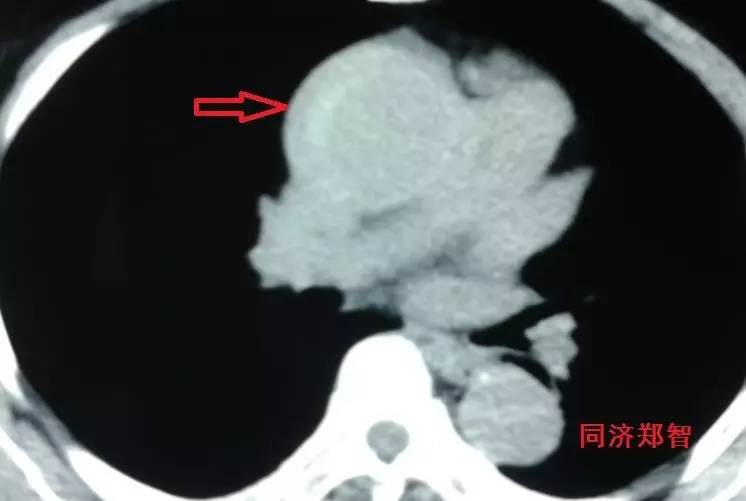

有时候平扫CT也能从血管内密度影的不同来诊断主动脉壁间血肿(图3)。平扫CT提示右肺动脉层面的升主动脉外侧为新月状稍亮的影(红箭头所示)。

图3

CT增强后证实为升主动脉壁间血肿(图4),如红箭头所示。

图4